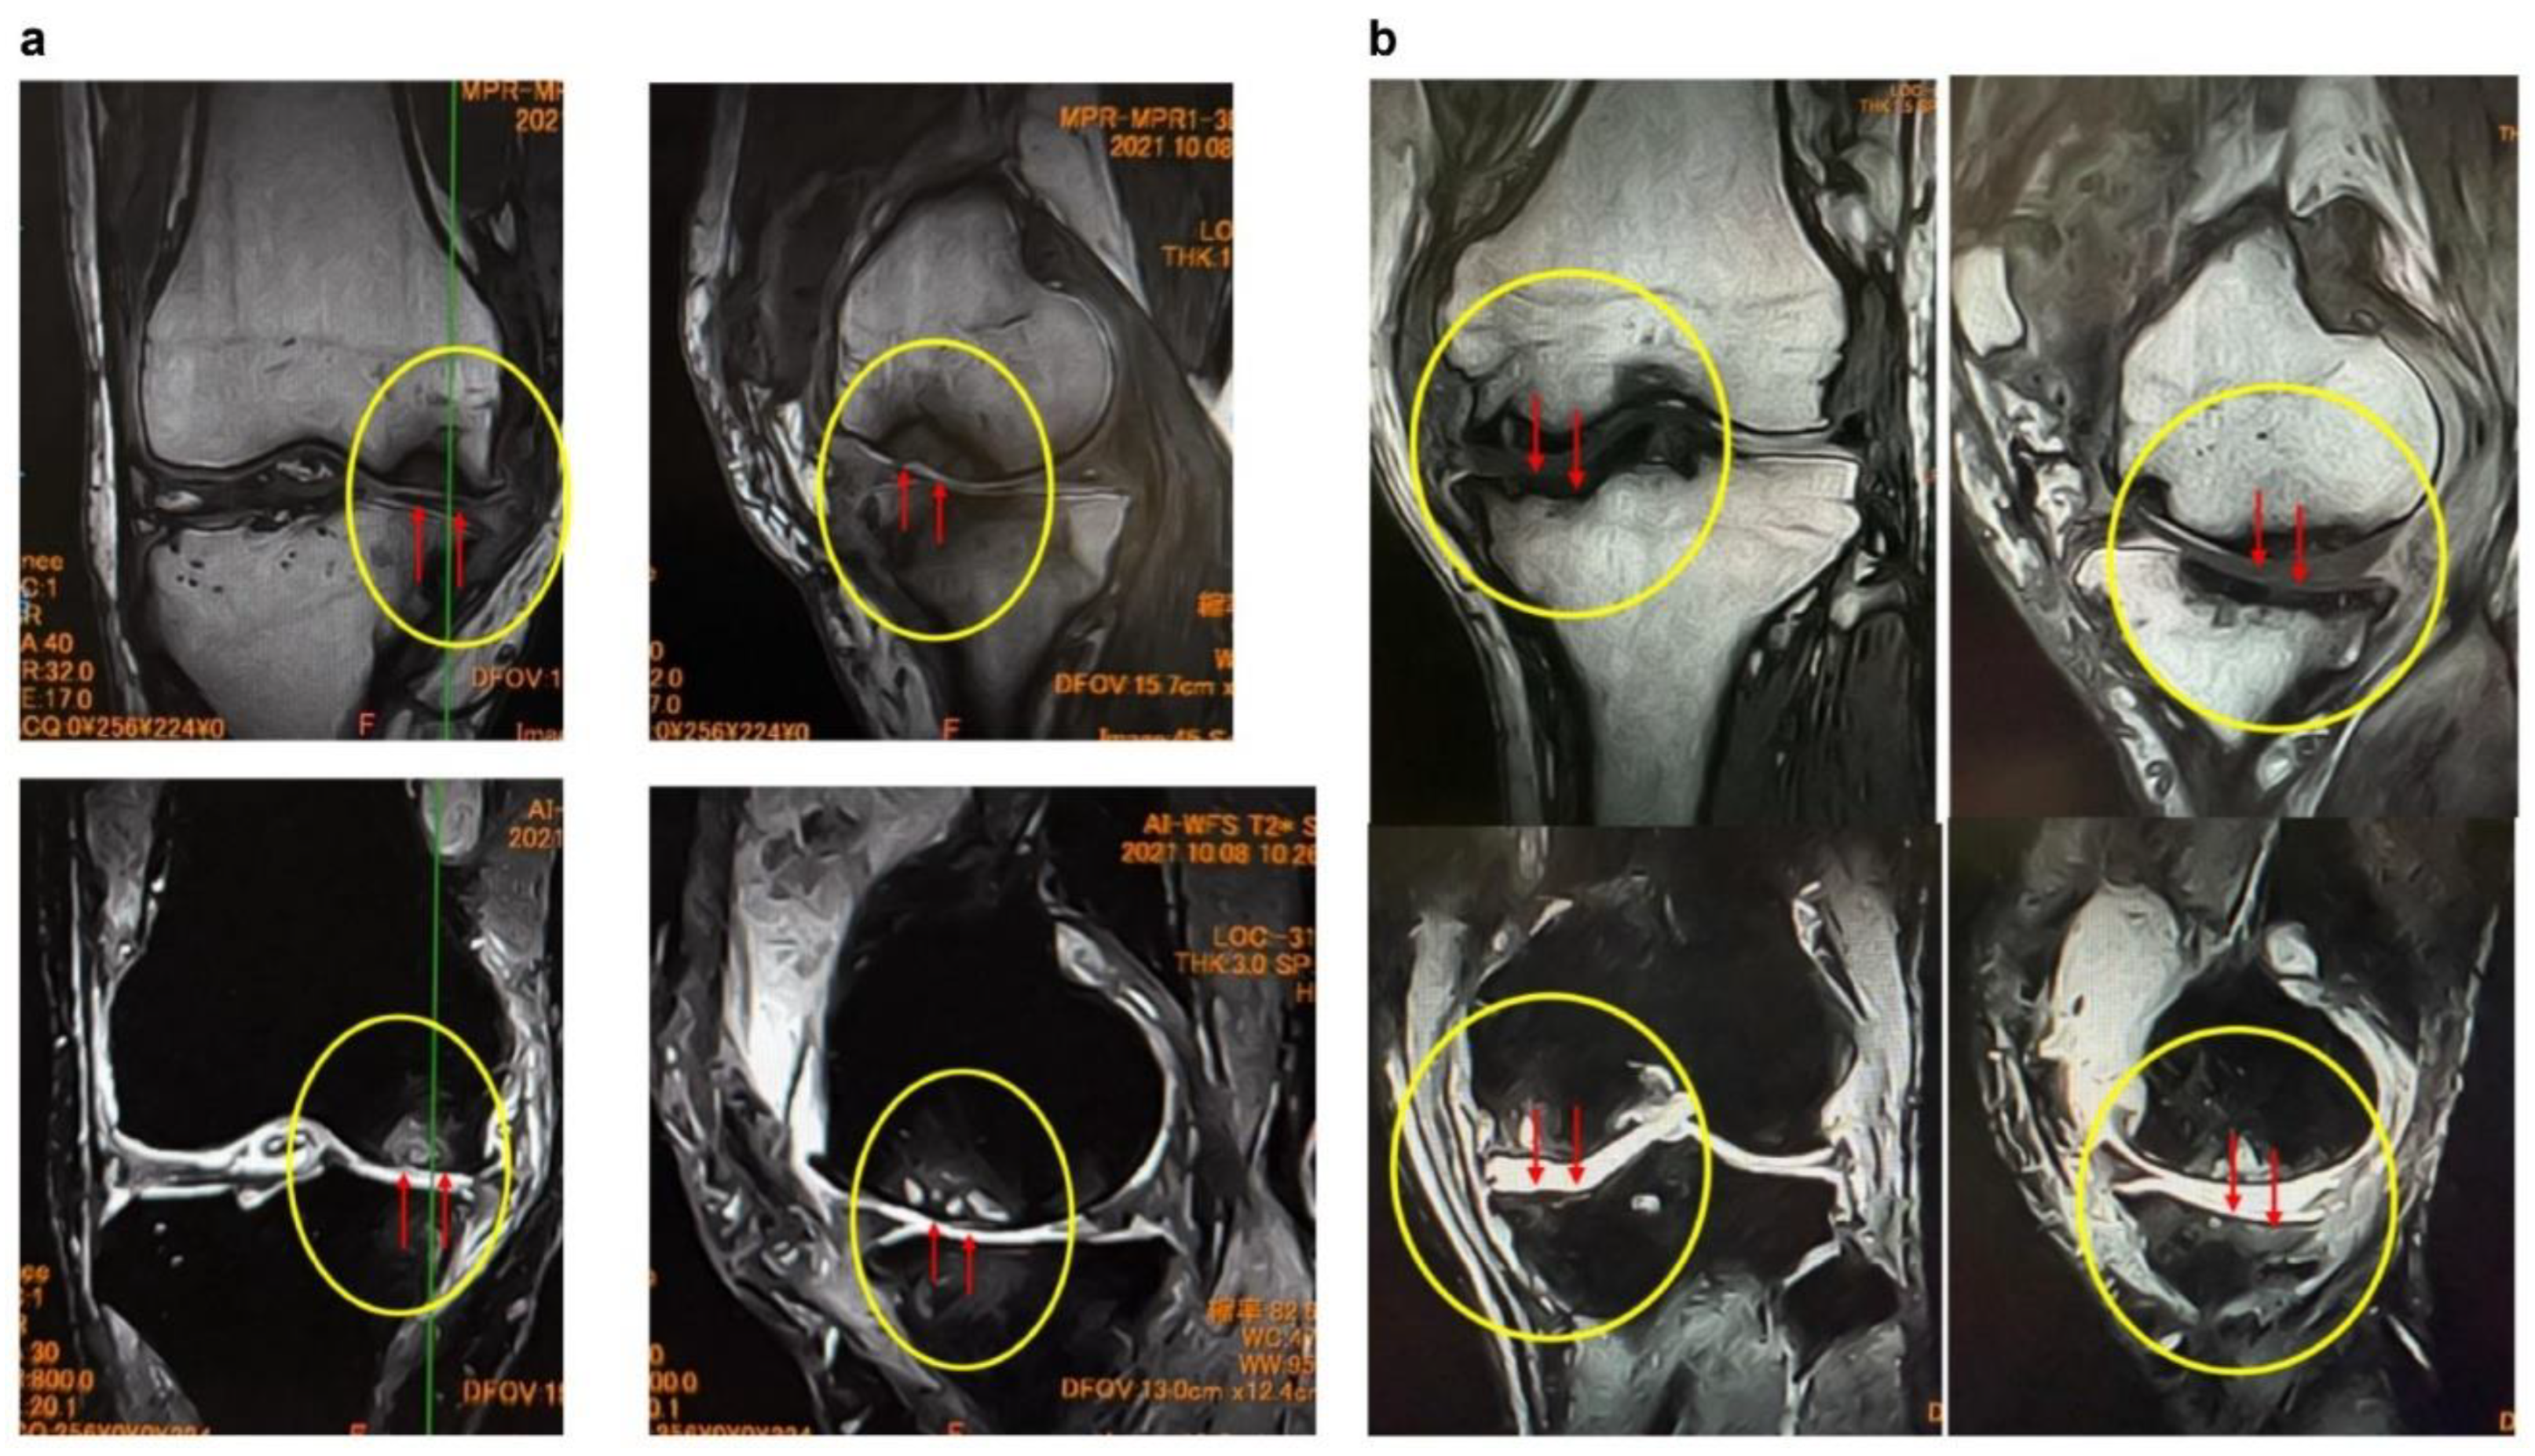

Figure 3.

MRI findings of (a) femoral articular surface collapse in the knee joint and (b). (a) Representative MRI images on T1-weighted and T2-weighted sequences (coronal and sagittal planes) are shown. In the area indicated by yellow circles, the articular surface exhibits marked irregularity with loss of cartilage continuity. At the sites indicated by red arrows, SBP disruption and cortical collapse are evident, demonstrating structural failure of the articular surface. Furthermore, on T2-weighted images, joint fluid signals extend into the bone marrow, suggesting the presence of bone marrow lesions (BML) and edematous changes within the subchondral bone. (b) MRI findings demonstrating tibial articular surface collapse. Coronal and sagittal T1- and T2-weighted MRI images are presented. In the regions outlined by yellow circles, the tibial articular surface exhibits marked irregularity, and at the sites indicated by red arrows, there is evident loss of continuity of the SBP with cortical depression and collapse of the articular surface. On T2-weighted images, the hyperintense joint fluid signal extends into the bone marrow, suggesting the presence of BMLs and associated edematous changes.